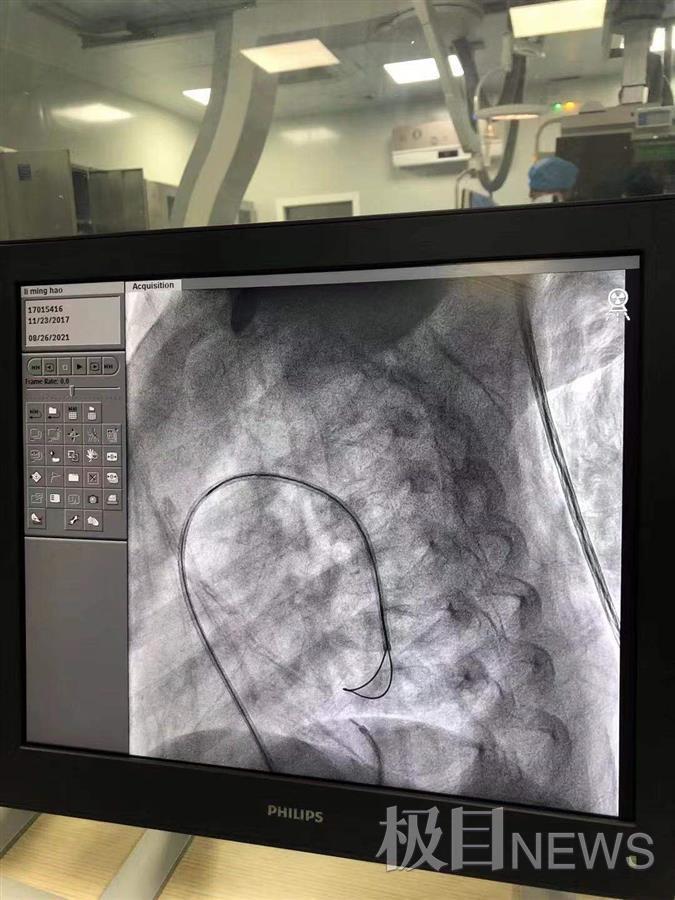

由于彭彭的动脉导管呈长漏斗型,最窄处内径小于2mm,若采用传统的从静脉端将导丝和导管穿过动脉导管未闭的方式建立轨道,完成难度极大且风险高。8月26日下午,东院区儿科心血管团队为患儿实现“逆行抓捕”:通过动脉端导入超滑导丝,让细若游丝的导管在小小的心脏中穿行,在静脉端通过抓捕器抓捕导丝后,将导丝拉入动脉,建立动静脉轨道。随着封堵器的展开,电脑显示屏上可见封堵器顺利植入患儿动脉导管未闭处。术后造影检查封堵器位置良好,未见残余分流。彭彭被送回病房后,各项生命体征平稳,术后第二天就可以下地活动了。